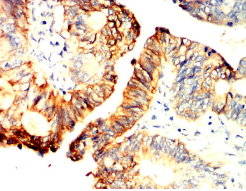

IHC    1/200 - 1/1000